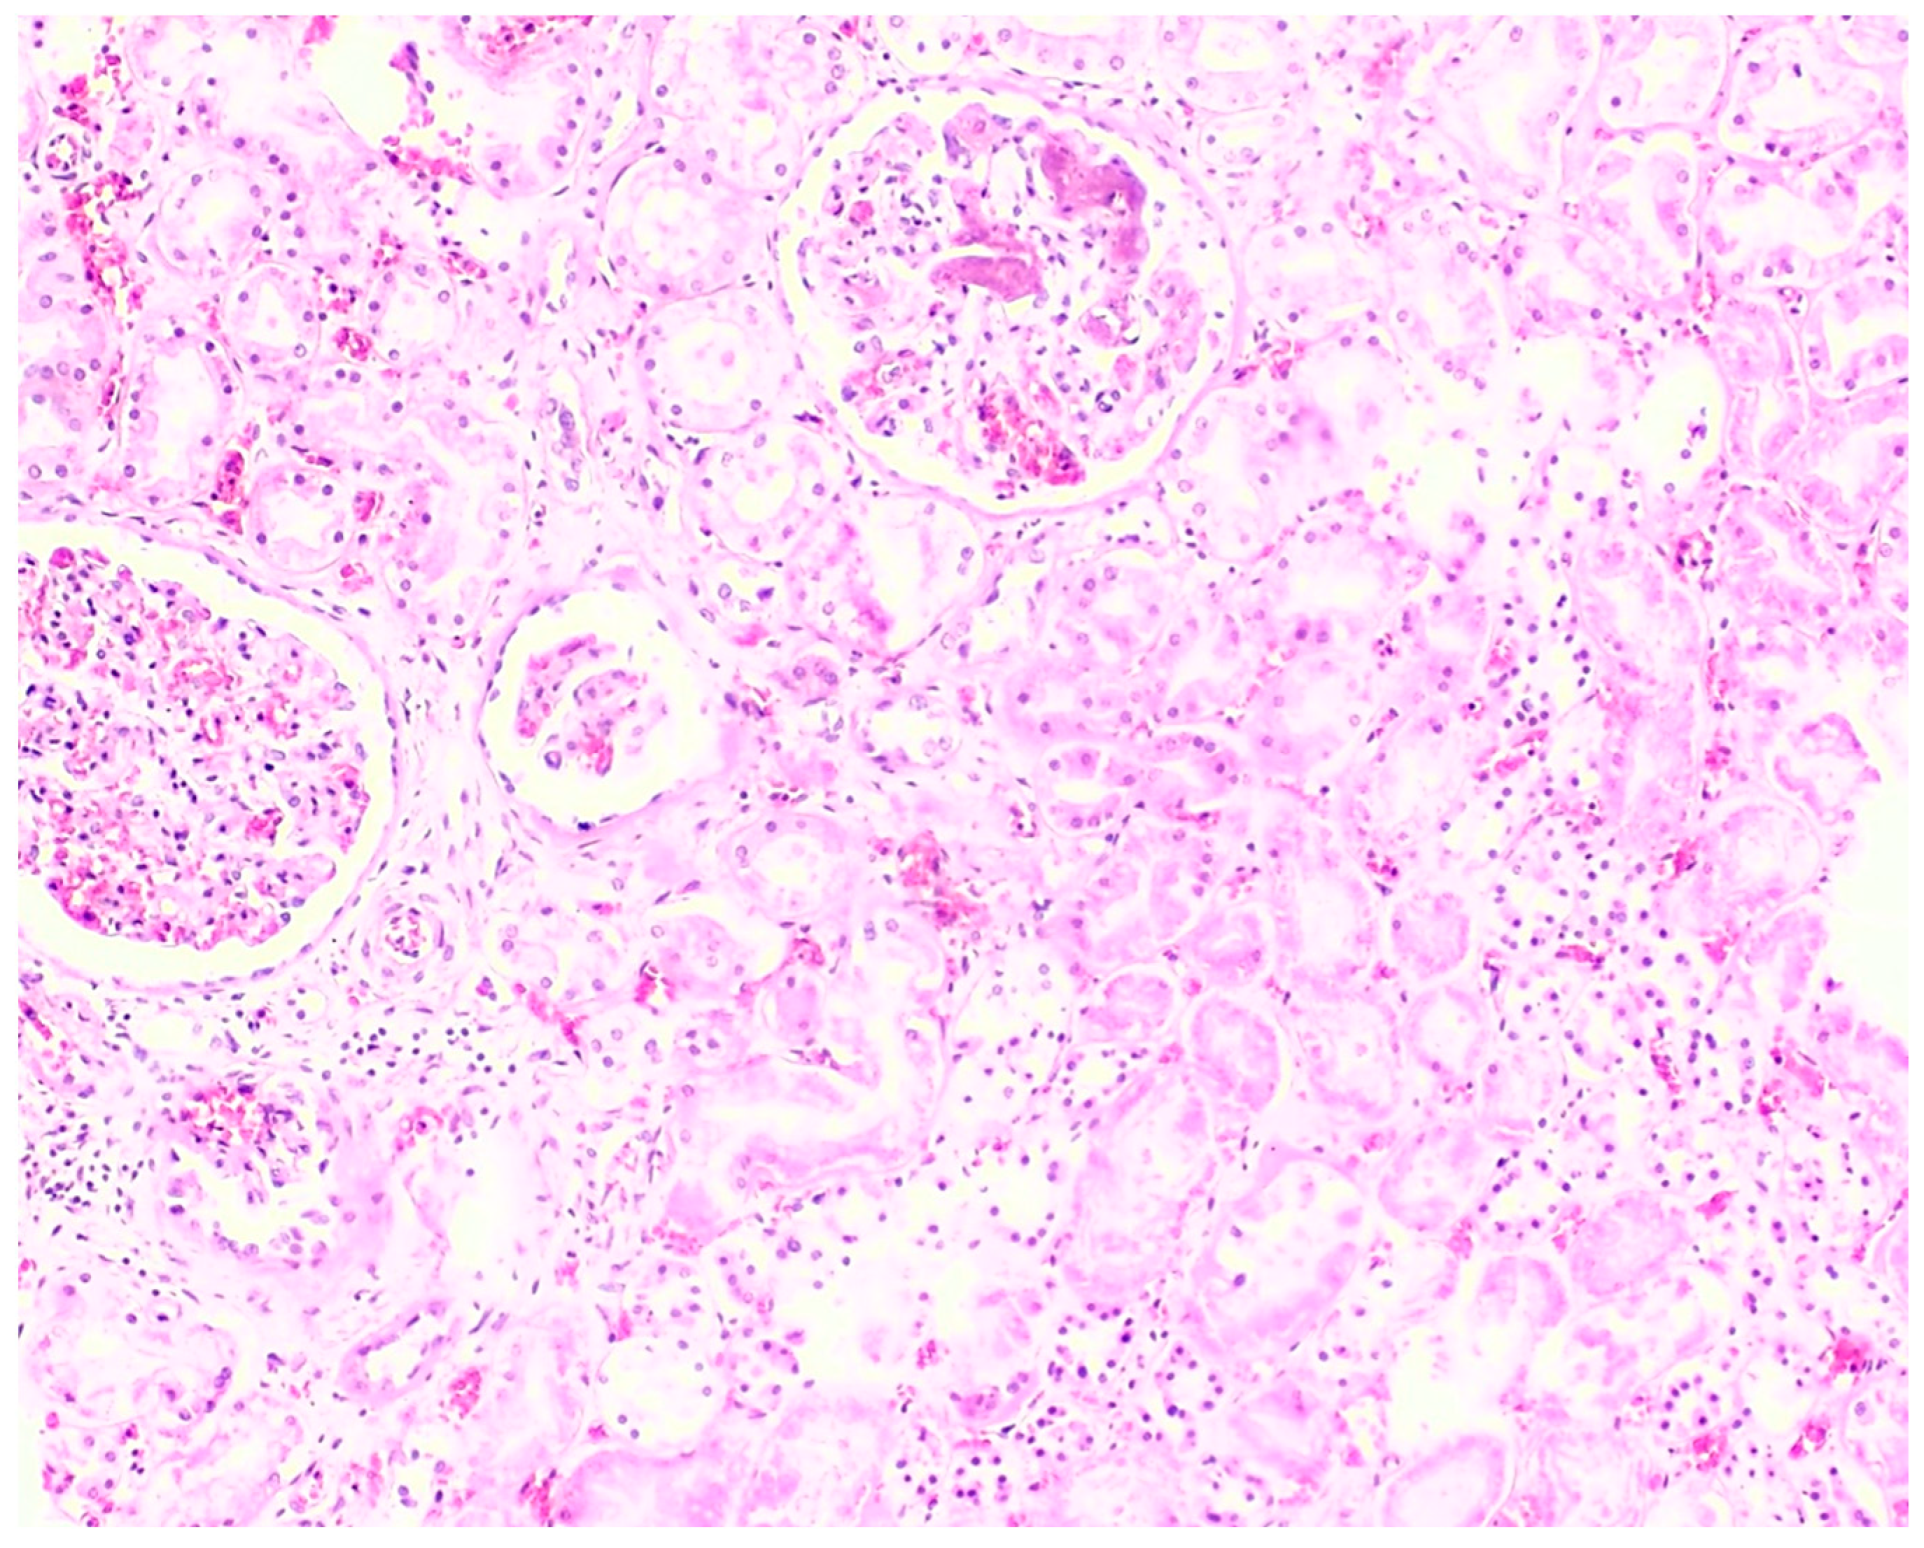

3.2. Microscopic Histopathological Findings

| Autopsy Case No. | Brain | Heart | Lung | Liver | Spleen | Kidney | Adrenal Gland | Esophagus/ Stomach |

|---|---|---|---|---|---|---|---|---|

| 1 | N/A | Hemorrhage at subendocardial and myocardium | Edema | Steatosis | N/A | Partial autolysis | Partial autolysis | N/A |

| 2 | N/A | N/A | N/A | Steatosis | N/A | N/A | N/A | N/A |

| 3 | Subarachnoid congestion, hemorrhage, eosinophilic neurons | Thrombosis, myocardial necrosis, focal subendocardial hemorrhage, atherosclerosis | Diffuse alveolar damage, fibrin platelet thrombi | Multifocal ballooning degeneration (hepatocyte), steatosis | Congestion | Acute tubular necrosis, fibrin platelet thrombi in glomeruli | Focal cortical necrosis | Mucosal infarct, hemorrhage |

| 4 | N/A | N/A | Edema, congestion, petechial hemorrhage | Steatosis | Congestion | N/A | N/A | Mucosal hemorrhage, esophagitis |

| 5 | N/A | Atherosclerosis | Diffuse alveolar damage, hemorrhage, fibrosis | Cholestasis | N/A | Acute kidney injury | N/A | N/A |

| 6 | N/A | Myocardial infarction, coronary occlusion | Edema, congestion, petechial hemorrhage | N/A | N/A | N/A | Lipid depletion | Mucosal infarct, hemorrhage |

| 7 | Red blood cells within the subarachnoid space | Cardiomegaly, hemorrhage at myocardium | Edema, congestion, | Steatosis | Congestion | N/A | Lipid depletion of cortical cells | Superficial mucosal hemorrhage |